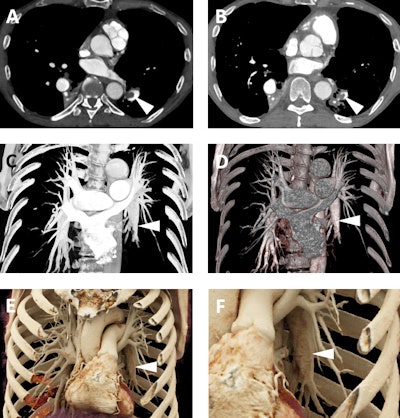

A 92-year-old man with a history of aortic stenosis initially treated with an open surgical procedure to place a bioprosthetic aortic valve and subsequently revised by endovascular replacement of a CoreValve. A-C: Volume-rendered images demonstrate the CoreValve (white arrowheads) inside the bioprosthetic valve (white arrows). The patient also has a patent saphenous vein-to-left anterior descending artery bypass graft (thin white arrow in C). D-F: Cinematic-rendered images also demonstrate the CoreValve (black arrowhead in D and white arrowheads in E and F) within the older bioprosthetic valve (black arrow in D and white arrow in E). The patient's patent saphenous vein graft is also apparent in D (thin black arrow). The photorealistic quality of the volume-rendered images may find eventual application in aiding vascular surgeons and other interventionalists by allowing the diagnosis of subtle thromboses or other valve-related pathologies that are not as apparent with less detailed visualizations.